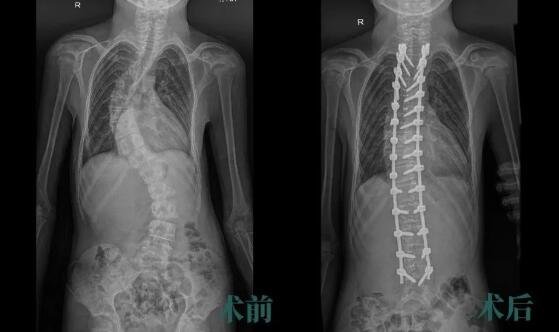

完善术前准备,在麻醉科和神经电生理监测医护等的精心配合下,朱晓东教授全程指导,尚军主任医师、孟磊副主任医师组成的手术团队顺利完成手术,用时约2小时40分。

术后,为取得更好的矫形效果,脊柱外科医护团队联合康复科帮助小俊进行快速康复、肢体功能锻炼等治疗。一周后,小俊即可佩戴胸腰支具下地活动。

沉重的‘罗锅’不到3个小时就‘卸掉’了!小俊重新“挺直腰杆”,还意外收获约5cm的身高,等待他的将是美好的未来。

小俊脊柱畸形术后得到了明显的纠正